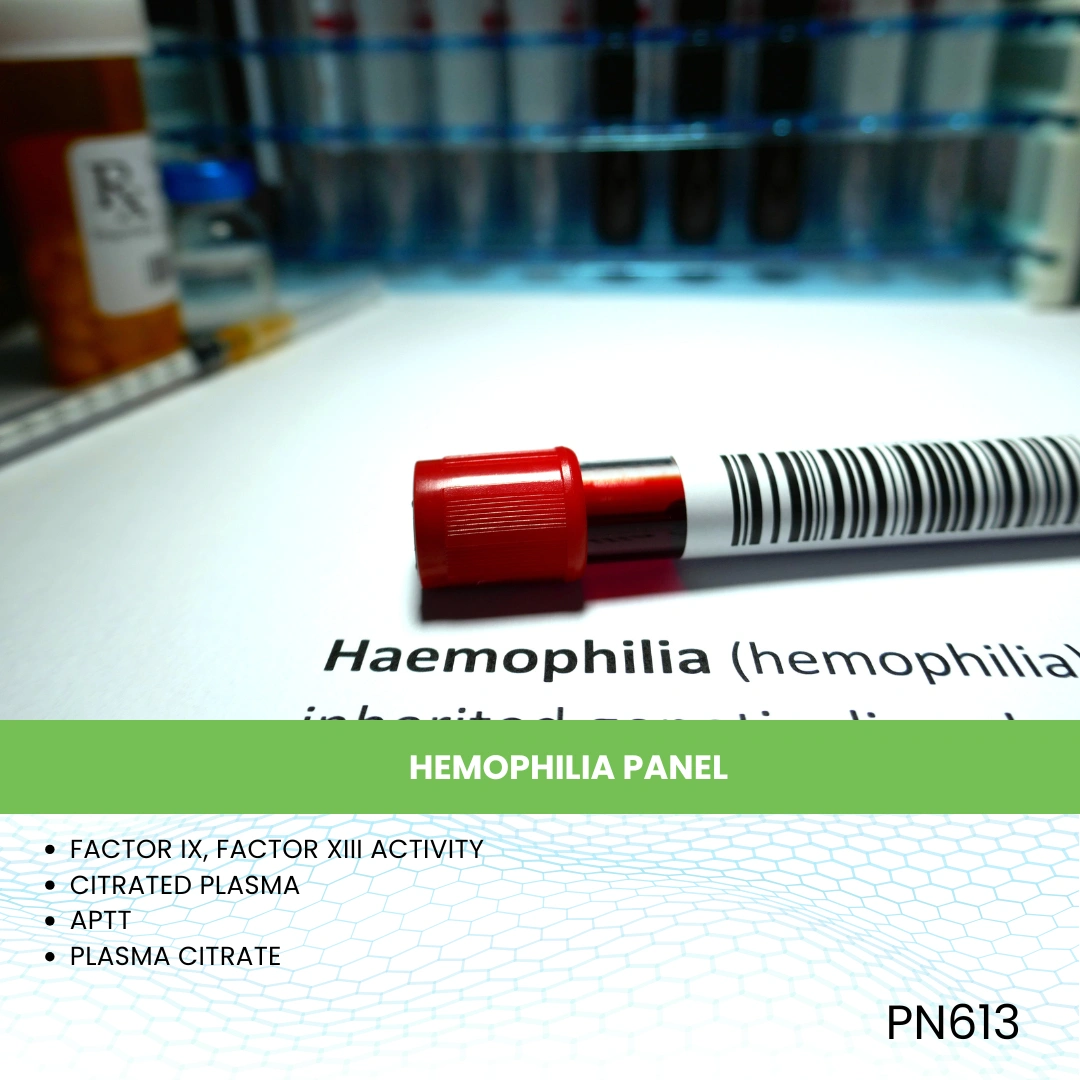

- Blood Test

- Blood Test